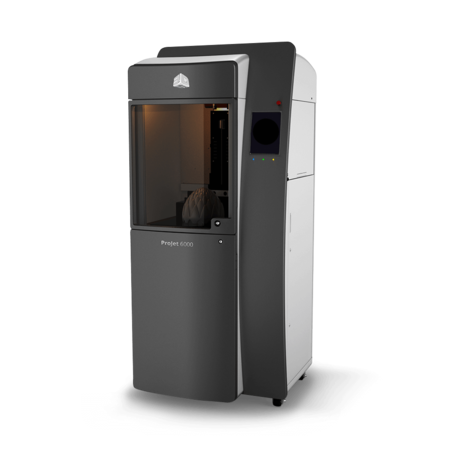

Once the model is completed, the doctors create a prototype (on a 3D Systems, Inc. SLA® 3D printer) made of epoxy resin. For implants, this prototype is then sent to a lab that uses the output to mold an implantable part, quite similar to the way dentures are made. Once this part has been completed the center either hand carries the part or sends it via overnight delivery depending on the hospital that ordered it.